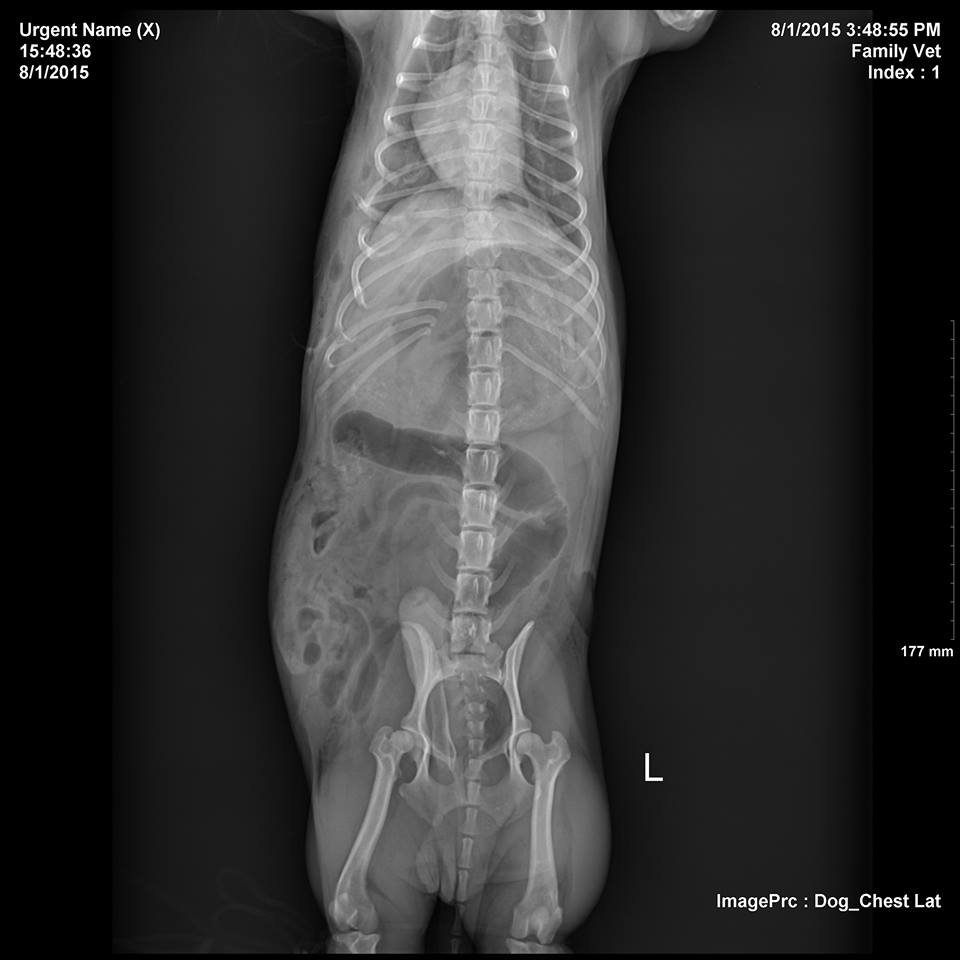

First appearances can be deceiving as there were just a few puncture wounds to the skin. The bite had caused a hernia, a tear in the muscle wall, if left his intestines might pass through and become occluded. X rays showed six broken ribs. Costa was in a serious condition and was rushed to surgery as soon as he was stable for anesthesia. There was no guarantee the little dog would survive. The hernia was repaired without complication but the chest injuries were much more complicated than was anticipated. Under the small bite holes the muscle was severely traumatized with more holes leading straight into the chest cavity. Once these were uncovered Costa could no longer breathe for himself and he had to be manually ventilated under controlled anesthesia whilst his ribs were wired and all of the tears in his chest muscle were sutured. It was a long surgery but the plucky pup pulled through. Even with two types of IV antibiotic and daily cleaning of the wounds Costa still battled infection from his bites. It took almost 2 weeks of hospitalization before he could be discharged and his ribs and muscles are still healing.